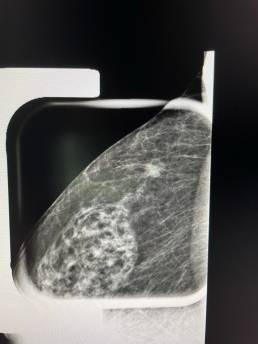

Stable appearance compared to 2018. Ultrasound didn’t show any suspicious images. MammoScreen® pointed to a right axillary lesion consistent with fibro glandular mass but persistent on spot compression view.

Additional MRI was performed and found a contrast-enhancing mass with irregular contours.

The biopsy was in favor of an infiltrating carcinoma.

MammoScreen can help assess lesions that may be mistaken for lymph nodes.